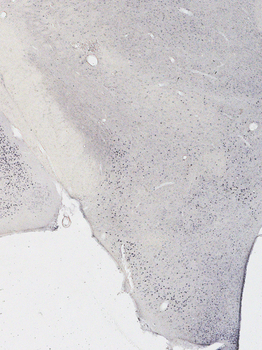

Immunostaining of 25μm thick cryosections of PFA-perfused Mouse Amygdala, antigen retrieval with citrate buffer Ph 6 at 80°C for 30 min, HRP-staining with Ni-DAB after Biotin-SP-antigoat amplification.